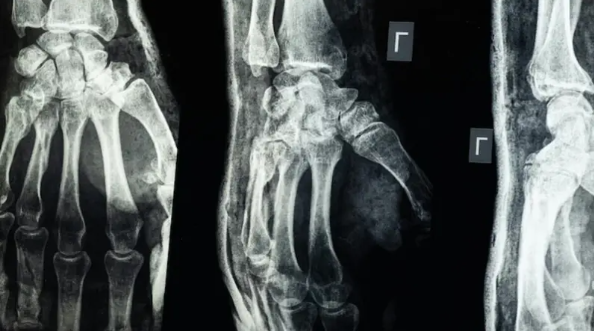

لا داعي لزراعة المسامير والصفائح .. "غراء طبي" يجبر العظام المكسورة في "3 دقائق" فقط

وأوضح أن هذا الغراء يتميز بقدرته على جبر العظام بطريقة سريعة ودقيقة حتى في بيئة غنية بالدم، مع ميزة إضافية كونه يُمتَص طبيعياً من الجسم أثناء عملية الالتئام، ما يلغي الحاجة إلى عمليات جراحية لاحقة لإزالة المسامير أو الصفائح المعدنية.

وأكدت الاختبارات المعملية أن Bone-02 نجح في تحقيق نتائج جيدة من حيث السلامة والفعالية. وفي إحدى التجارب، أُجريت العملية في أقل من 180 ثانية (ثلاث دقائق)، بينما كانت طرق العلاج التقليدية تتطلب وقتاً طويلاً لزرع صفائح فولاذية ومسامير.

وبحسب الاختبارات المعملية، تمكن الغراء من تحقيق قوة ربط تفوق 400 رطل، وقوة قص تبلغ نحو 0.5 ميغاباسكال، وقوة ضغط تقارب 10 ميغاباسكال. كما أظهرت التجارب على أكثر من 150 مريضاً نتائج ناجحة، ما يعزز احتمالية أن يصبح بديلاً للزراعات المعدنية التقليدية التي تُستخدم في تثبيت العظام. كما يقول العلماء إنه قد يقلل أيضًا من مخاطر العدوى.